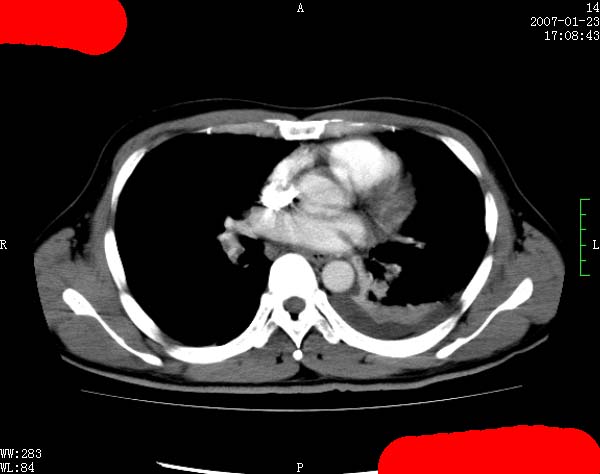

以下是引用jiangjing在2007-1-24 23:35:00的发言:[br]支持 增强扫描见右肺动脉干、左下肺动脉见充盈缺损。印象为:1、右肺动脉干、左下肺动脉栓塞。 2、左侧胸腔积液合并左肺下叶被动性肺不张。

以下是引用rjg199343在2007-1-24 23:22:00的发言:[br]增强扫描见右肺动脉干、左下肺动脉见充盈缺损。印象为:1、右肺动脉干、左下肺动脉栓塞。 2、左侧胸腔积液合并左肺下叶被动性肺不张。